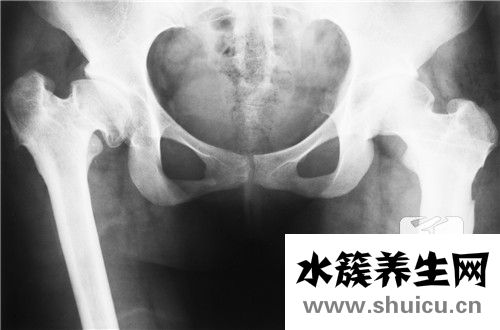

由于强烈的对撞碰撞,很少发生髋关节脱位,许多人患有先天性髋关节脱位。 先天性髋关节属于四肢畸形,可能发生股骨头坏死和关节僵硬等术后并发症。 由于treatment突在治疗过程中被严重挤压,下肢及其肱...